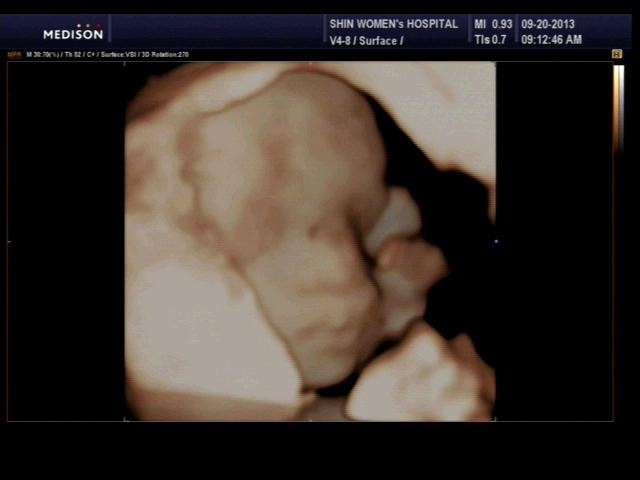

30ÁÖ ¶§ ÃÔ¿µÇÑ ÀÔüÃÊÀ½ÆÄ¿¡¿ä^^

¿ï º¹´óÀÌ´Â ºÎ²ô·³ÀÌ ¸¹Àº ¾Æ°¡Àΰ¡ ºÁ¿ä. Àú »çÁøµµ ¸î ¹ø ½Ãµµ ³¡¿¡ °Ü¿ì °ÇÁø °Å¶ø´Ï´Ù